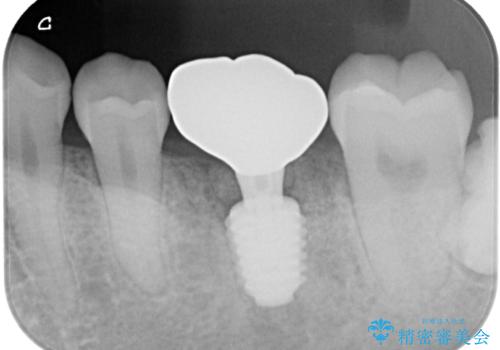

インプラント埋入時に植立具合の安定性を測定したところ、十分な数値が得られたため、速やかに仮歯を装着して咬合回復をさせることができました。

抜歯を含めた外科処置を1回に抑えることができ、あっという間に治療を終えることができました。